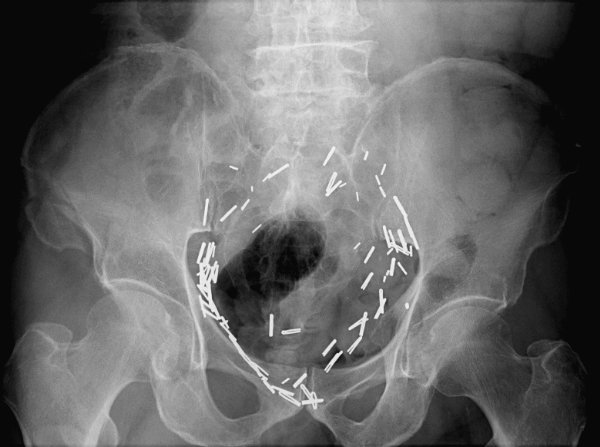

Return to Duverney Fracture